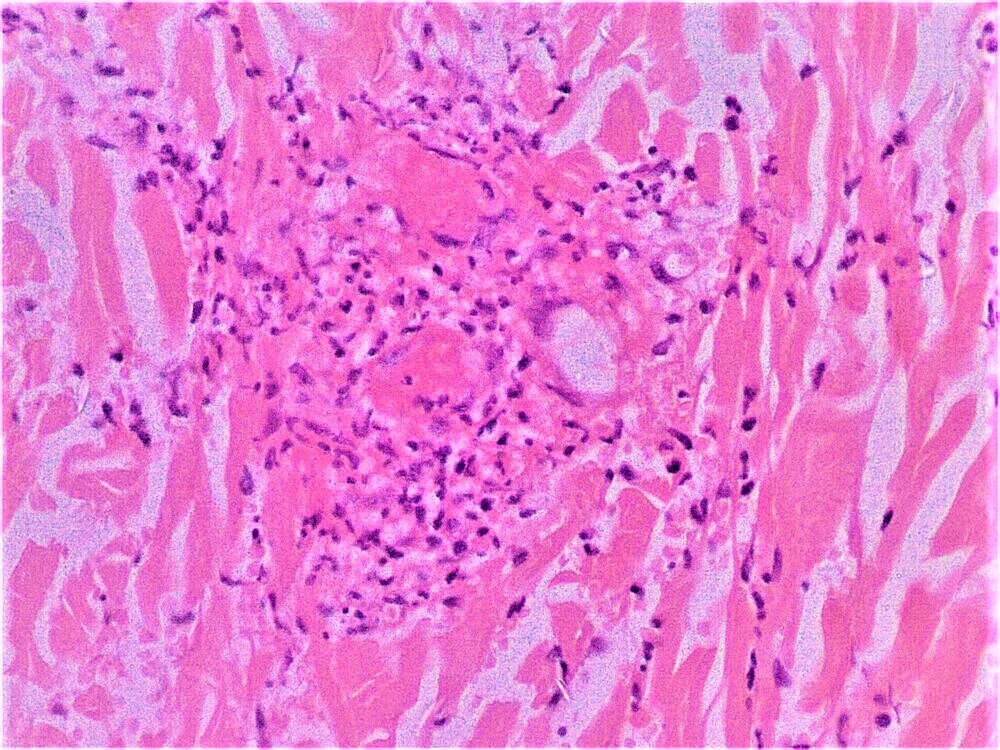

Microscopic (histologic) description

- Erythema nodosum-like lesions: septal panniculitis; vasculitis (lymphocytic or neutrophilic) and necrobiosis may be found

- Pathergy reaction: perivascular infiltrate of mononuclear cells; mast cell infiltrate and neutrophilic vasculitis may be found

- Reference: Patholog Res Int 2012;2012:209316

Microscopic (histologic) images

- Comment: Septal panniculitis with unremarkable epidermis. Dermis shows moderate perivascular lymphocytic infiltrate. The subcutaneous fat demonstrates widening of the fibrous septa with edema and infiltration of lymphocytes and histiocytes. Spillover of infiltrate to the adjacent fat lobules is present. Small focus of lymphocytic vasculitis is noted.